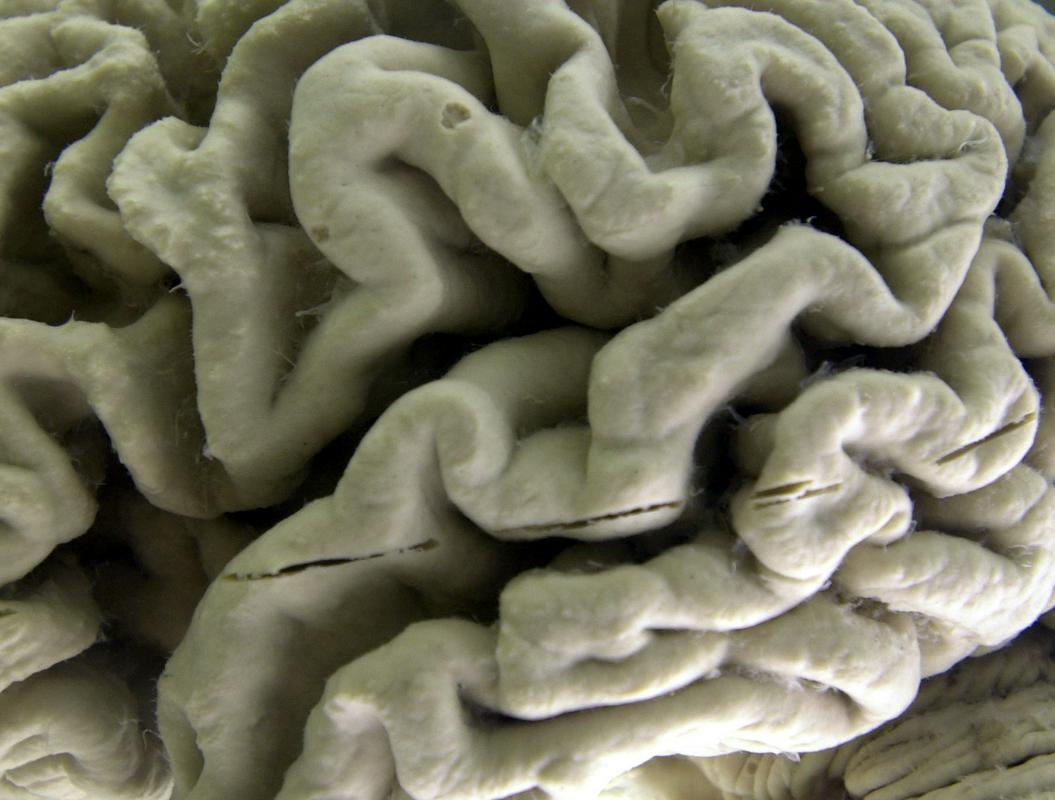

Lecanemab je zdravilo iz protiteles, zasnovano za odstranjevanje lepljivih usedlin beljakovine amiloid beta, ki se kopičijo v možganih bolnikov z Alzheimerjevo boleznijo.

Podjetje Eisai je ob tem sporočilo, da so se pri 68 odstotkih udeležencev možgani očistili beljakovine amiloid. Zdravilo je tudi znižalo raven beljakovine tau, ki tvori nevarne skupke v možganskih celicah.